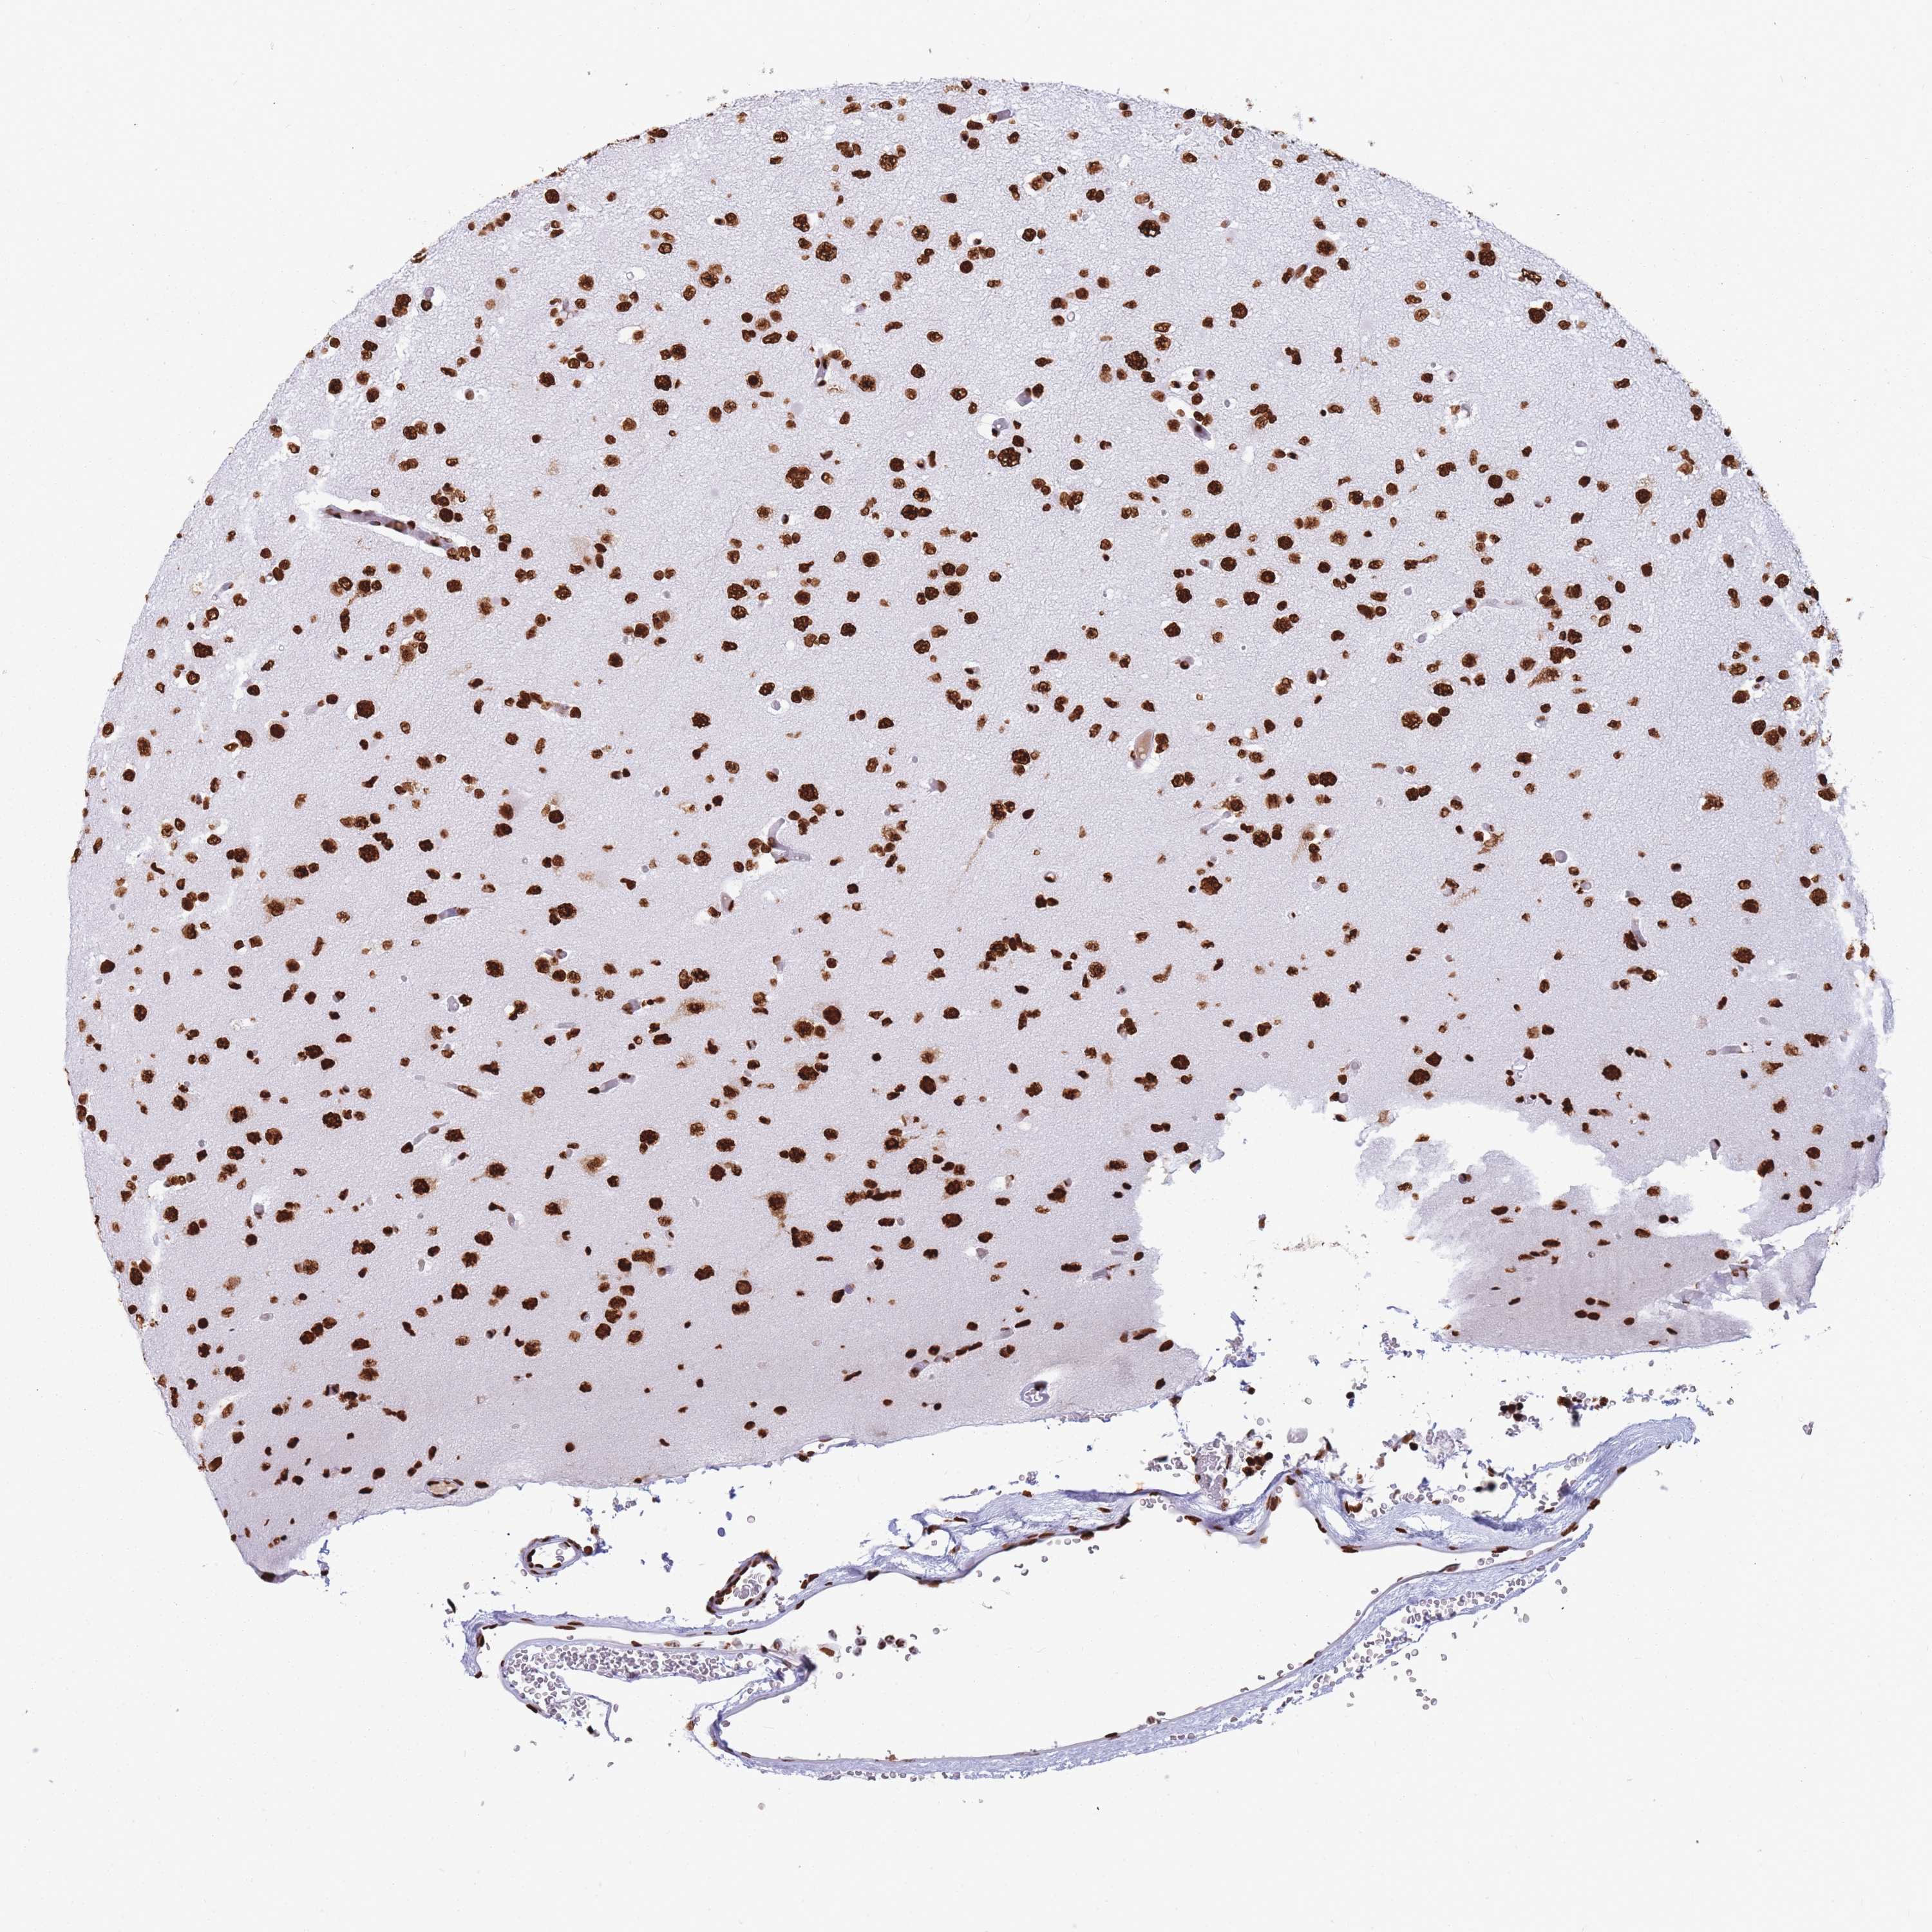

GLIOMA - Protein expressioni

A mouse-over function shows sample information and annotation data. Click on an image to view it in a full screen mode. Samples can be filtered based on level of antibody staining by selecting one or several of the following categories: high, medium, low and not detected. The assay and annotation is described here.

Note that samples used for immunohistochemistry by the Human Protein Atlas do not correspond to samples in the TCGA dataset.

Antibody stainingi

Antibody staining in the annotated cell types in the current human tissue is reported as not detected, low, medium, or high, based on conventional immunohistochemistry profiling in selected tissues. This score is based on the combination of the staining intensity and fraction of stained cells.

Each image is clickable and will lead to virtual microscopy that enables deeper exploration of all samples and also displays staining intensity scores, fraction scores and subcellular localization as well as patient and tissue information for each sample.

Antibody HPA046290

Antibody HPA049475

Antibody CAB046477

Staining

High

Medium

Low

Not detected

Intensity

Strong

Moderate

Weak

Negative

Quantity

>75%

75%-25%

<25%

None

Location

Nuclear

Cytoplasmic/membranous

Cytoplasmic/membranous,nuclear

Glioma, malignant, High grade

Glioma, malignant, Low grade